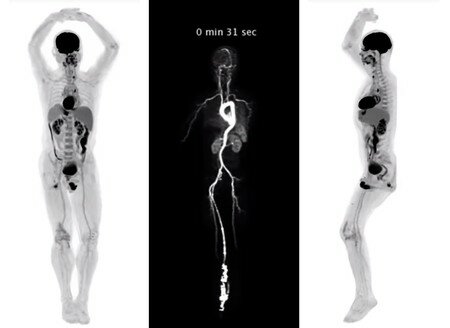

El principio de traslación y rotación fue conservado, el número de detectores aumento a 30 y el tiempo de adquisición de datos disminuyo a 20segundos. La traslación era más rápida y se utilizó para estudiar tórax y abdomen. Se hablaba por primera vez de un tomógrafo de cuerpo entero.

Aparición de la sexta generación, cuando Kalender y sus colaboradores inventaron la tomografía en espiral.

Se caracteriza porque hay un movimiento continuo de la camilla a través del gantry (parte del tomógrafo en continua rotación que contiene el tubo de rayos X y el arreglo de detectores).

Introducción de modelos de séptima generación: tomógrafos multi-tajadas, también llamados multi-detectores. Estos equipos se caracterizan, principalmente, por tener arreglos multidimensionales (varias líneas de detectores) y se basan en la geometría de tercera generación, aunque, en este caso, en lugar de un rayo en forma de abanico, el rayo tiene forma de cono.